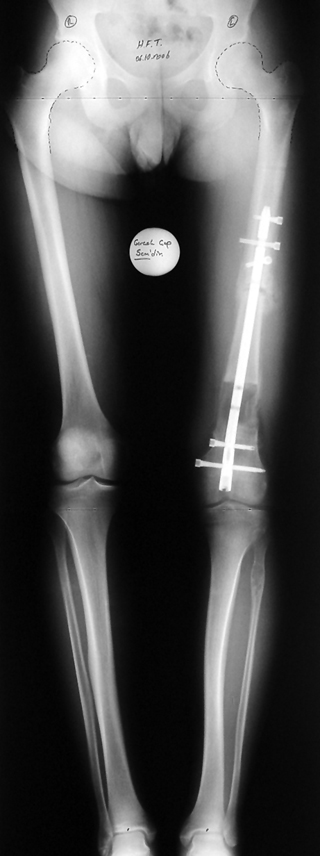

Bu Bacak Kısalık tipi bir kırığın kısalmış pozisyonda kaynaması ile oluşur. Bir çok vaka yetişkinlerde görülür ve sadece bir uzatma ile tedavi edilebilir. Ek deformiteler de aynı anda düzeltilebilir. Bu hastaların çoğu çivi üzerinden uzatma veya tam implante edilen çivi ile tedavi edilebilirler.

Vaka 3